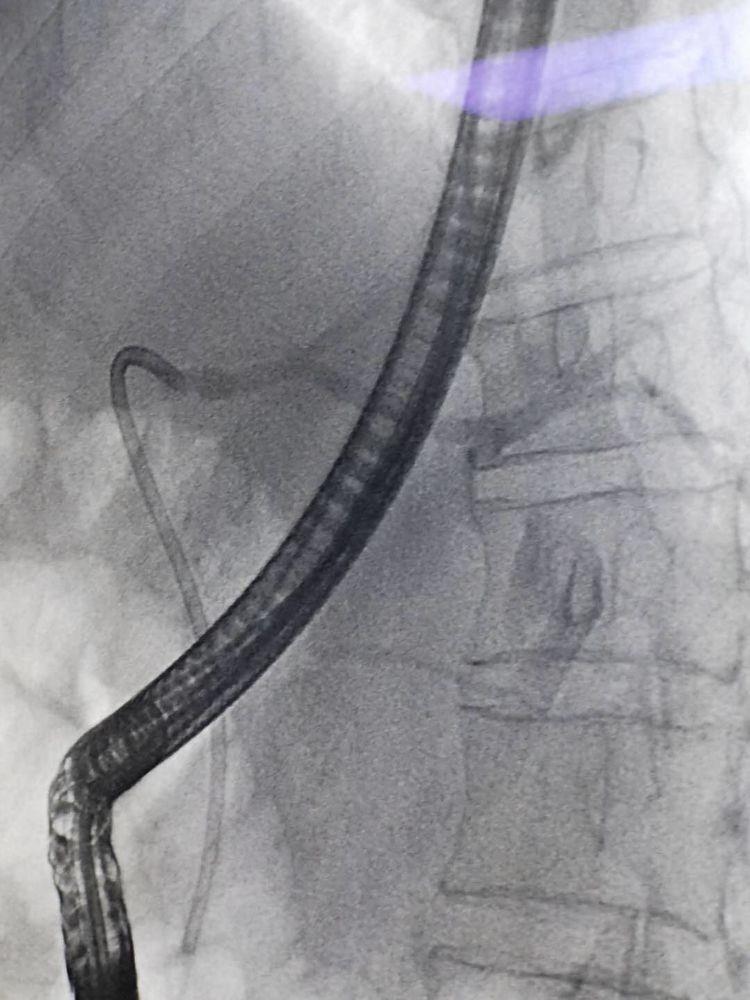

术中造影示:胆总管下段充盈中断

术中造影示:支架置入成功